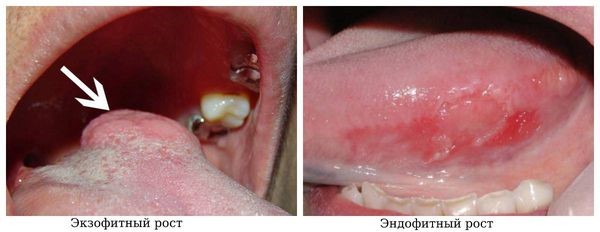

Рак слизистой оболочки полости рта имеет три формы роста:

- Экзофитный — больший компонент опухоли растёт над слизистой оболочкой, выглядит как бляшкообразный, грибовидный нарост с чёткими границами.

- Эндофитный — опухоль распространяется вглубь без чётких границ, выглядит как язва или уплотнение.

- Смешанная форма.